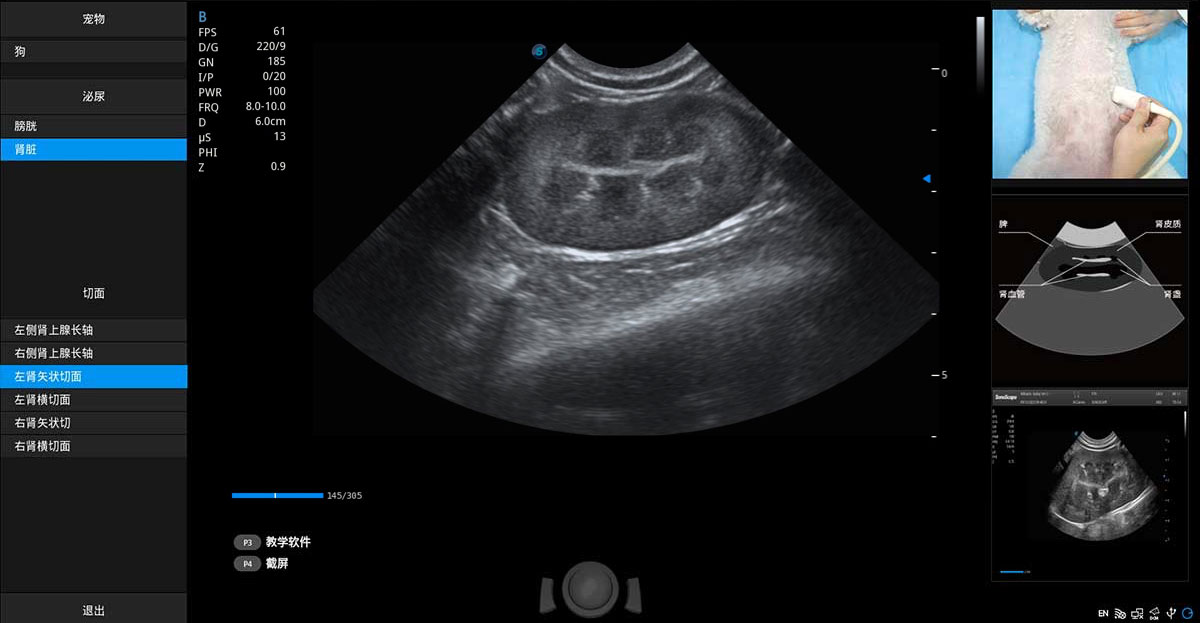

ProPet 80 專為動物醫(yī)生設計,對不同的動物體型和生理結(jié)構(gòu)作出了針對性的優(yōu)化。通過動物影像專用軟件,可滿足個性化的應用需求,幫助動物醫(yī)生獲得更精確的診斷數(shù)據(jù)。

提供解剖示意圖、標準超聲圖像、掃查手法涂和操作者實時檢查圖像,指導操作者進行標準切面的正確掃查。

針對寵物、馬科、農(nóng)場動物、實驗室動物和異寵等20多種動物種類,預置豐富的動物注釋及動物體標庫。